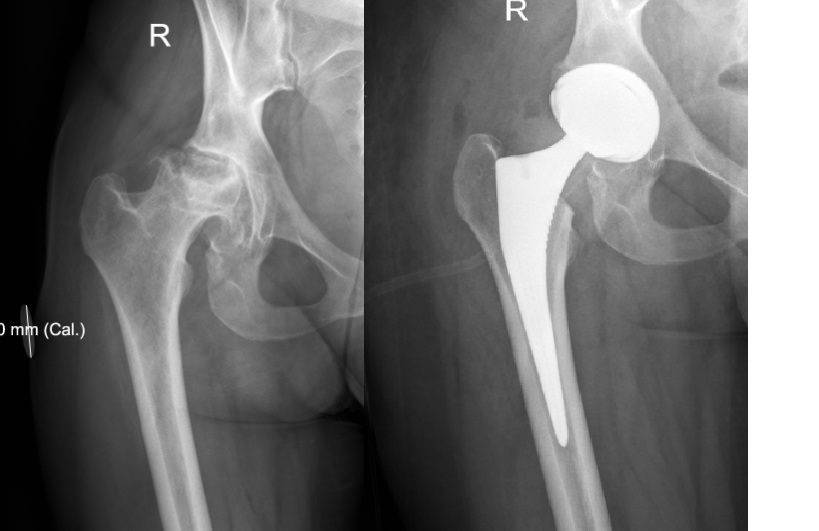

За последние 2-3 года прооперировал пациентов 8 молодого возраста с АНГБК из "бывших". У 3 точно все хорошо, одна умерла через 2 года после операции, остальных активно не вызывал, сами тоже не звонят... такой опыт с ними.

Проблемы с ними бывают, безусловно, один сбежал сразу после синтеза лодыжек, зимой в тапочках, но и отказать как-то тоже не могу... вот снимки девушки 27 лет с АНГБК, оперировал на прошлой неделе. Клянется, что "завязала"... дай Бог! Дочке 2 года...